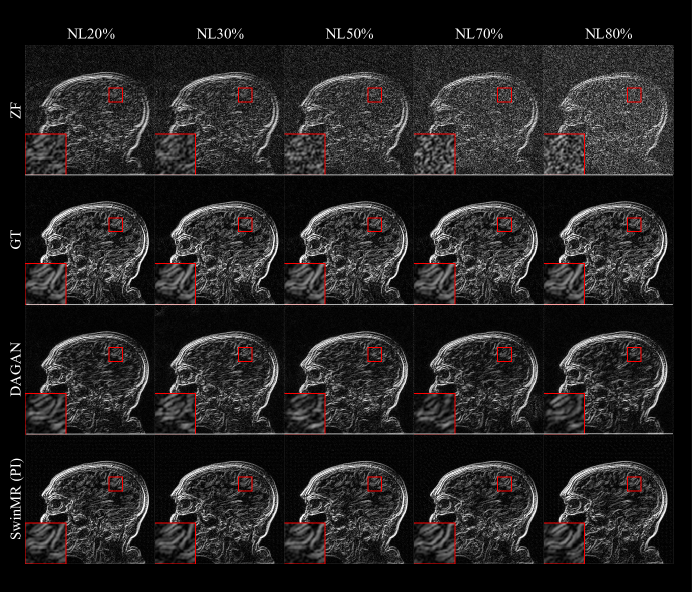

The quantitative results of the noise experiments are shown in Figure 9 and Table 3. The sample of reconstructed images, edge information and absolute differences of standardised pixel intensities (10×10\times) between reconstructed images and GT images are shown in Figure 10, Figure 11 and Figure 12, respectively.

According to the results, under the interruption of noise, SwinMR maintains better reconstruction quality compared to DAGAN. The quality improvement becomes more clear when under a high noise level.

Figure 11: Edge information of the experiment on different noise using Gaussian 1D 30% mask. Five noise levels (NL20%, NL30%, NL50%, NL70% and NL80%) were tested in this experiment. Row 1: Edge information of undersampled zero-filled MR images (ZF) with different noise levels; Row 2: Edge information of ground truth images (GT); Row 3: Edge information of reconstructed MR images by DAGAN; Row 4: Edge information of reconstructed MR images by SwinMR (PI). The edge information was extracted by the Sobel operator.